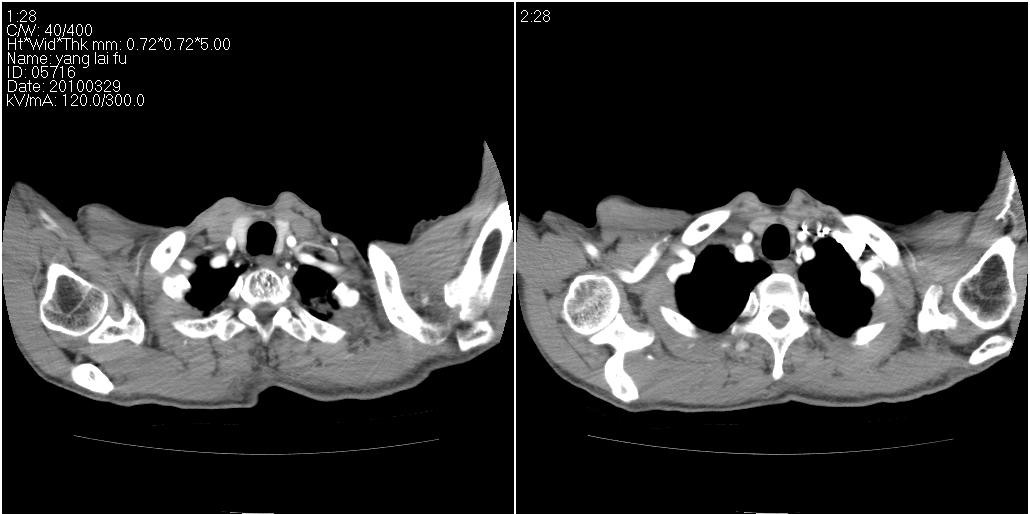

以下是ct检查的情况:

标题: ct增强: